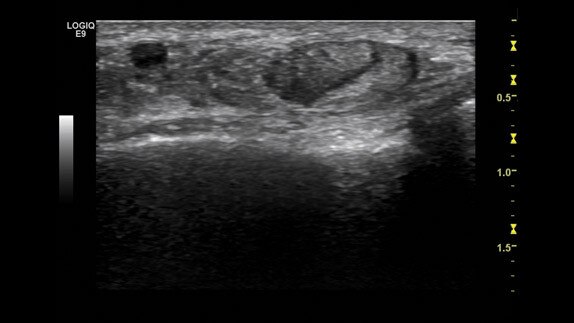

ML6-15 Melanoma